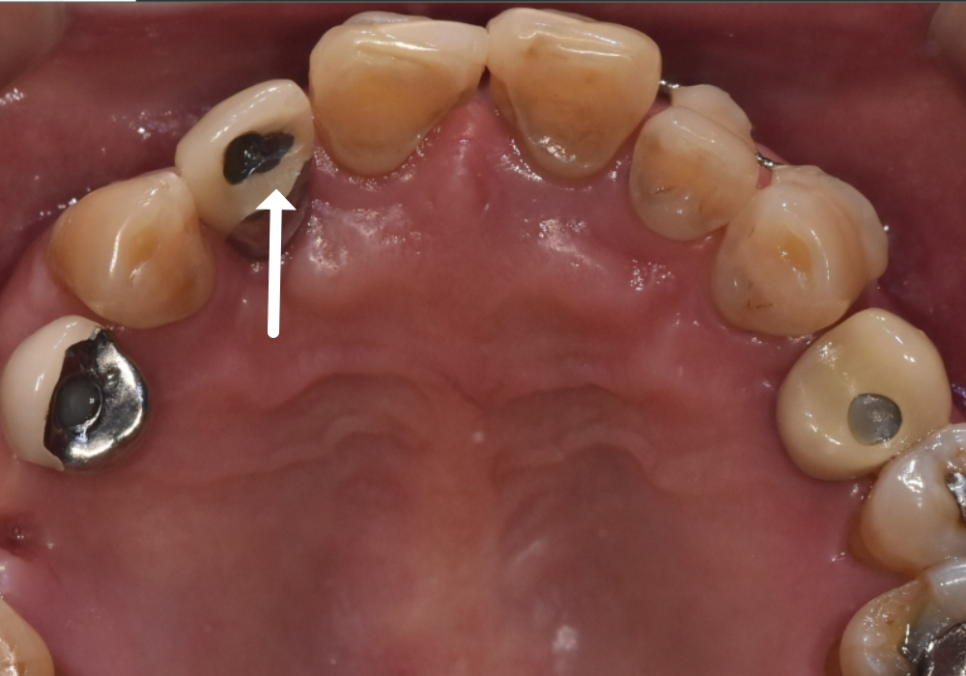

앞니가 너무 흔들리다 보니,

흔들리는 앞니 3개를

왼쪽 송곳니에 철사로

연결(스플린트) 해서 생활하고 계셨어요.

스플린트는 쉽게 말하자면,

흔들리는 치아들을

튼튼한 옆 치아랑 한 덩어리로 묶어서

힘을 나눠 받게 하는 방법입니다.

250106 스플린트로 묶인 치아

잠깐은 버틸 수 있지만,

근본 문제가 해결된 건 아니죠.

250106 임플란트 보철 깨짐

도자기 계열로 씌운 임플란트 크라운이

깨져있는 모습이 보였습니다.